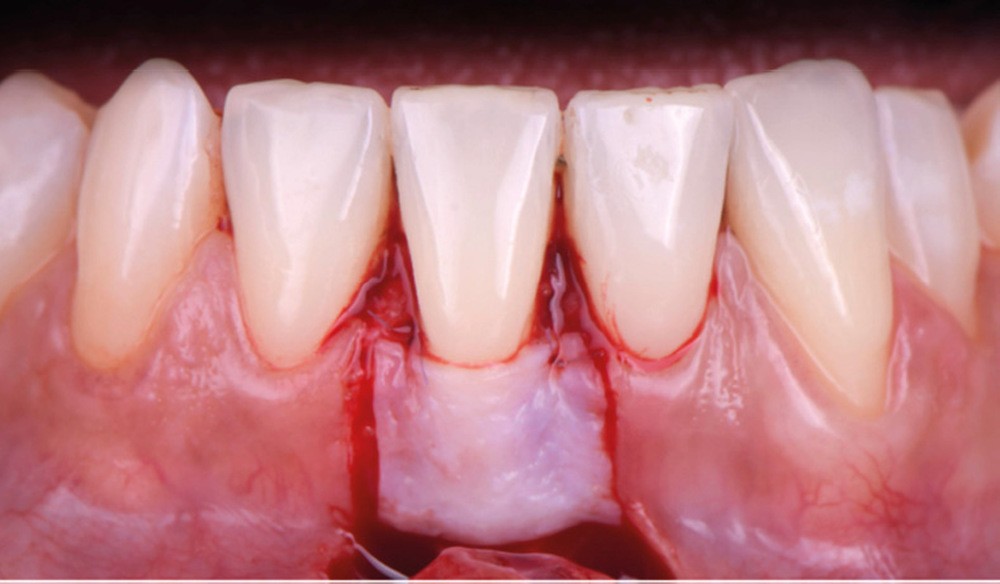

Le lambeau positionné coronairement associé à une greffe de conjonctif enfoui (fig. 1-4)

La stabilité du lambeau est primordiale dans la réussite de cette technique de recouvrement. En cas d’instabilité, même en l’absence d’erreurs techniques, l’analyse de certains facteurs liés au patient est indispensable. Afin de maintenir la stabilité du lambeau jusqu’à la dépose des points, le praticien doit veiller à l’adéquation du contrôle de plaque effectué par le patient, à l’absence de mastication impliquant la zone d’intervention, à la prévention de tout traumatisme ou de modifications des conditions locales par le patient.

Selon le Dr Sylvie Pereira, contrairement au maxillaire où la hauteur du lambeau déplacé coronairement est déterminée par la profondeur de la récession, à la mandibule, les incisions horizontales sont placées de manière à obtenir au moins 2 mm de tissu…